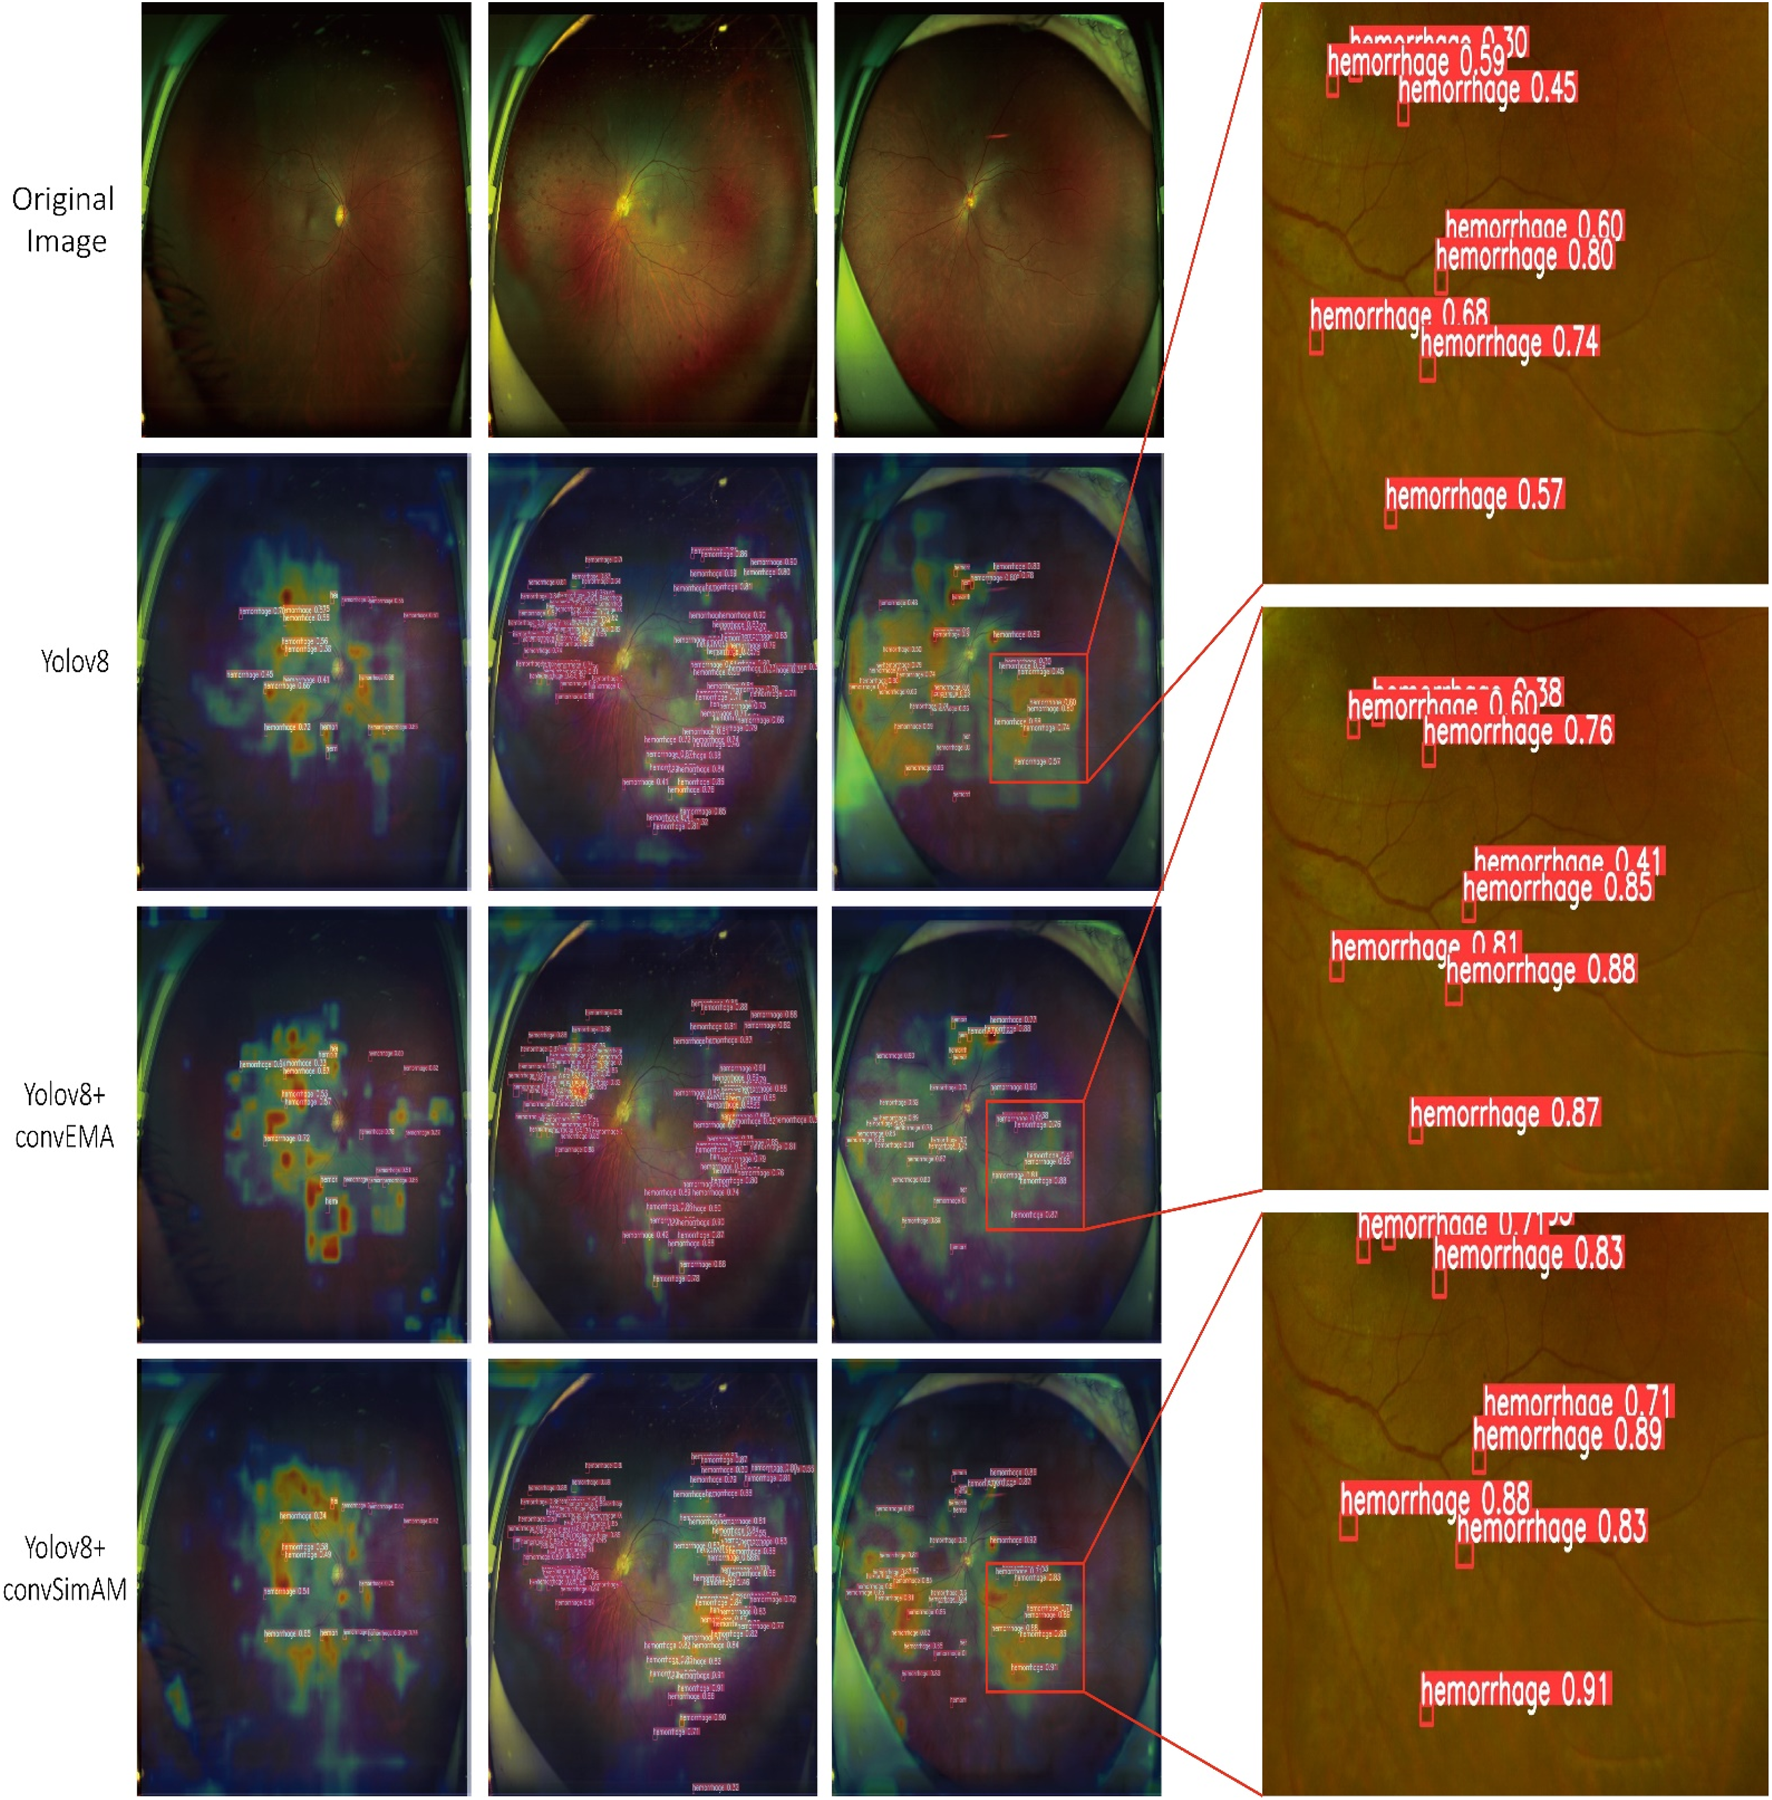

Based on model training and evaluation, we obtained detection results for four types of DR lesions: hemorrhages, hard exudates, cotton wool spots, and epiretinal membranes. These results were achieved using three model configurations: YOLOv8, YOLOv8+ convEMA, and YOLOv8+ convSimAM. The precision, recall, and AP metrics for each lesion type are presented in Table 1, providing a comprehensive comparison of model performance across the different lesion categories. Representative examples of lesion annotation outcomes are illustrated in Figure 4, demonstrating the model’s capability to localize and classify lesions in UWF fundus images.

FIGURE 4

Three distinct fundus images are presented in three columns, with four rows corresponding to different detection models. Each red bounding box delineates a detected lesion along with its associated confidence score.

4.2.3 Grad-CAM heatmap analysis

As illustrated in Figure 5 and Table 1, the activation maps of the YOLOv8 model generally encompass the lesion areas; however, the activations appear relatively dispersed. Some regions do not accurately focus on the features of the lesions, and background interference remains prominent. For hard exudates, the activation areas mostly align with the target; however, in the case of epiretinal membranes, the boundaries of activation are less distinct, and certain regions may be overlooked. In contrast, the YOLOv8+ convEMA model exhibits more concentrated activation in the lesion regions, with significantly reduced activation intensity in non-lesion areas. The delineation of target features is moderately improved; however, the detection of hemorrhages remains somewhat suboptimal. Compared to YOLOv8, background noise is markedly diminished, and the overall activation distribution appears more uniform. The YOLOv8+ convSimAM model demonstrates the most distinct activation patterns, featuring clearly defined lesion boundaries and minimal background interference. This model exhibits the highest proficiency in extracting lesion-related features, particularly for epiretinal membranes, where contrast and edge details are significantly enhanced.

FIGURE 5

Visualization of model predictions and interpretability using Grad-CAM and object detection. The Grad-CAM heatmaps presented on the left highlight the image regions that significantly influence the model’s classification of the lesion, where red and yellow tones indicate higher relevance. On the right, each red bounding box delineates a detected lesion along with its associated confidence score.

Overall, YOLOv8 serves as a stable baseline model, although its performance is somewhat limited. The integration of the EMA mechanism in YOLOv8+ convEMA significantly enhances the model’s capacity to identify target regions, leading to substantial improvements in the detection of complex lesions. Among the three models, YOLOv8+ convSimAM exhibits the best performance as its attention mechanism significantly enhances both detection precision and recall for specific lesion areas, making it the most comprehensive and effective model in this study.